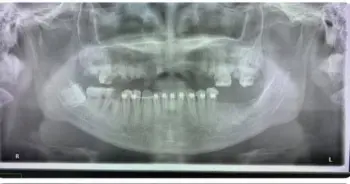

รีเทนเนอร์ คือ เครื่องมือที่ช่วยคงตำแหน่งของฟันไว้ ซึ่งมีความจำเป็นสำหรับผู้ที่ทำการเคลื่อนฟันด้วยการจัดฟัน แต่สำหรับผู้ที่ไม่ได้จัดฟัน การใส่รีเทนเนอร์ไม่ได้เกิดประโยชน์อะไรเลย แถมยังมีผลเสียอีกด้วย คือทำให้รูปฟันเสีย พูดไม่ชัด เหงือกเป็นแผล และรีเทนเนอร์ก็ยังเป็นอุปสรรคในการทำความสะอาด มีเศษอาหาร และเชื้อโรคสะสมได้ง่าย ซึ่งจะส่งผลให้เกิดฟันผุตามมา และยิ่งถ้าเป็นรีเทนเนอร์ที่ไม่ได้มาตรฐาน หรือรีเทนเนอร์แฟชั่นที่มีขายตามอินเตอร์เน็ต ก็ยิ่งเป็นอันตรายมากขึ้นไปอีก

อันตรายของรีเทนเนอร์แฟชั่น เกิดขึ้นได้ตั้งแต่ขั้นตอนการผลิต อย่างเช่น เรื่องของความสะอาด การใช้เครื่องมือซ้ำ จนเกิดการติดโรคต่างๆ หรือวัสดุที่ไม่ได้มาตรฐาน ที่อาจมีโลหะหนักเช่น สารแคดเมียม สารตะกั่ว ปนเปื้อนจนเกิดพิษต่อร่างกาย และหากเศษลวดหรือเครื่องมือบาดกระพุ้งแก้มหรือเนื้อเยื่อในปาก ก็อาจส่งผลให้เกิดการติดเชื้อในช่องปาก ลามไปถึงการติดเชื้อในกระแสเลือด,กระดูก และการเกิดแผลซ้ำๆ ยังเพิ่มความเสี่ยงต่อการเป็นมะเร็งช่องปากได้อีกด้วย

การเลือกทำรีเทนเนอร์ให้ปลอดภัย คือต้องเลือกทำกับคลินิกที่ได้มาตรฐาน และทำโดยทันตแพทย์ผู้เชี่ยวชาญเท่านั้น ไม่ควรสั่งทำ หรือสั่งซื้อรีเทนเนอร์สำเร็จรูปตามอินเตอร์เน็ต เพราะนอกจากจะไม่เกิดประโยชน์ต่อรูปฟันแล้ว อาจจะเกิดอันตรายที่รุนแรงถึงขั้นสูญเสียฟัน หรือถึงขั้นเสียยชีวิตได้เลย